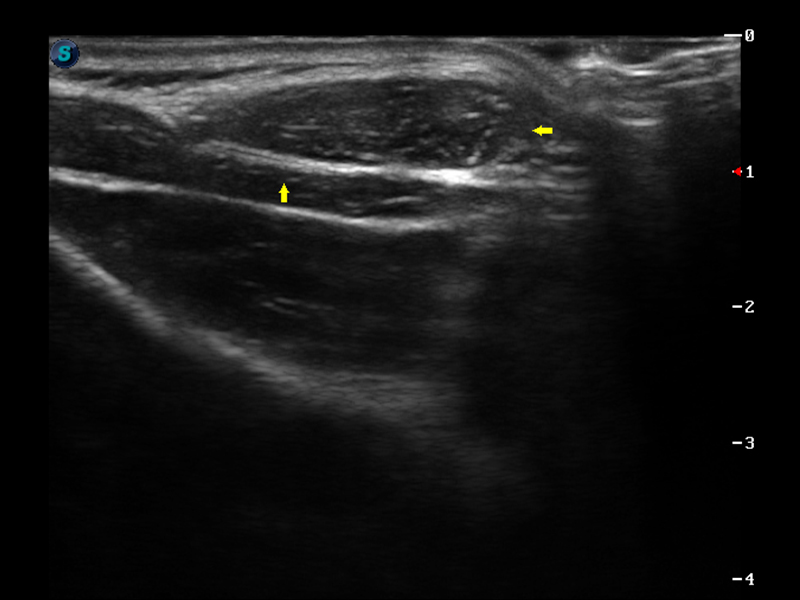

肌骨

肌纤维瘤